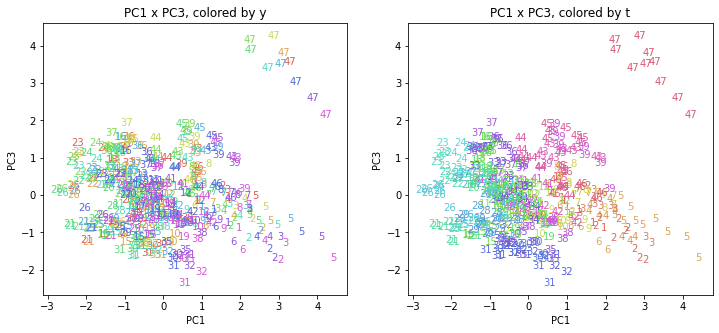

PCAの結果の第n主成分をPCnと表記します。

医療費データの場合と同様に、PCAの結果を見やすく表示するため、seabornのカラーパレットを使って、年月別、都道府県別に色分けして図示してみます(左側が年月別に色分け、右側が都道府県別に色分け)。PC1~PC8まで表示しました。

都道府県番号の表示

上の色分けだけでは都道府県が区別しにくいので、医療費データの場合と同様に、点の代わりに都道府県番号をプロットした図も描いておきます(色分けは上と同じ)。

医療費データの場合ほどはっきりとはしていませんが、PC2が概ね時間の経過を表す成分で、残りの成分が時点によって変わらない地域の特徴を表す成分となっているようです。

また、PC1×PC3を見ると、47沖縄が他の都道府県からかなり離れたところに位置しており、沖縄の地域差が際立っているのが分かります。これは、以前別の記事で年齢階級のない健診データでPCAを実行した場合と似た結果となっています。